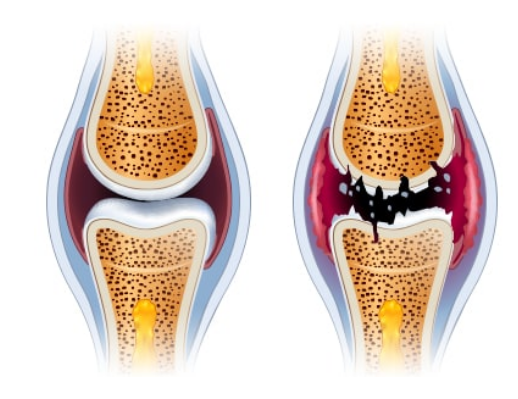

이미 망가진 관절은 되돌리기가 쉽지 않아요. 망가지기 전에 소중한 관절을 관리하고 보호해야겠습니다.

"연골은 지우개와 같아. 한번 닳아 없어진 연골은 다시 생성되지 않아. 미리미리 관리하는게 중요해 "